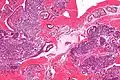

Micrographie d'endomètre décidualisé en raison de progestérone exogène. Coloration HE.